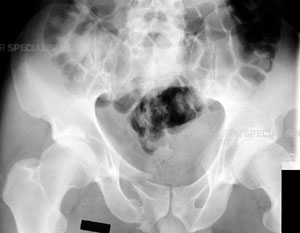

Radiograph of the pelvis demonstrating a fracture of the pubic bone

The complex nature of these fractures can be better understood by looking at the anatomy that is involved. The pelvis is made up of several bones (ileum, ischium and pubic bones) which create a bony ring, meeting at the pubic symphysis in the front and the sacrum (a bone situated at the lower end of the spine) in the back. Together with a number of ligaments and muscles, the bones of the pelvis support the weight of the upper body and rest on the hip joints. The pelvis protects abdominal organs including the intestines and the bladder, as well as major nerves and blood vessels. Pelvic fractures may occur at any location on the bones depending on the nature of the accident and the areas of impact.